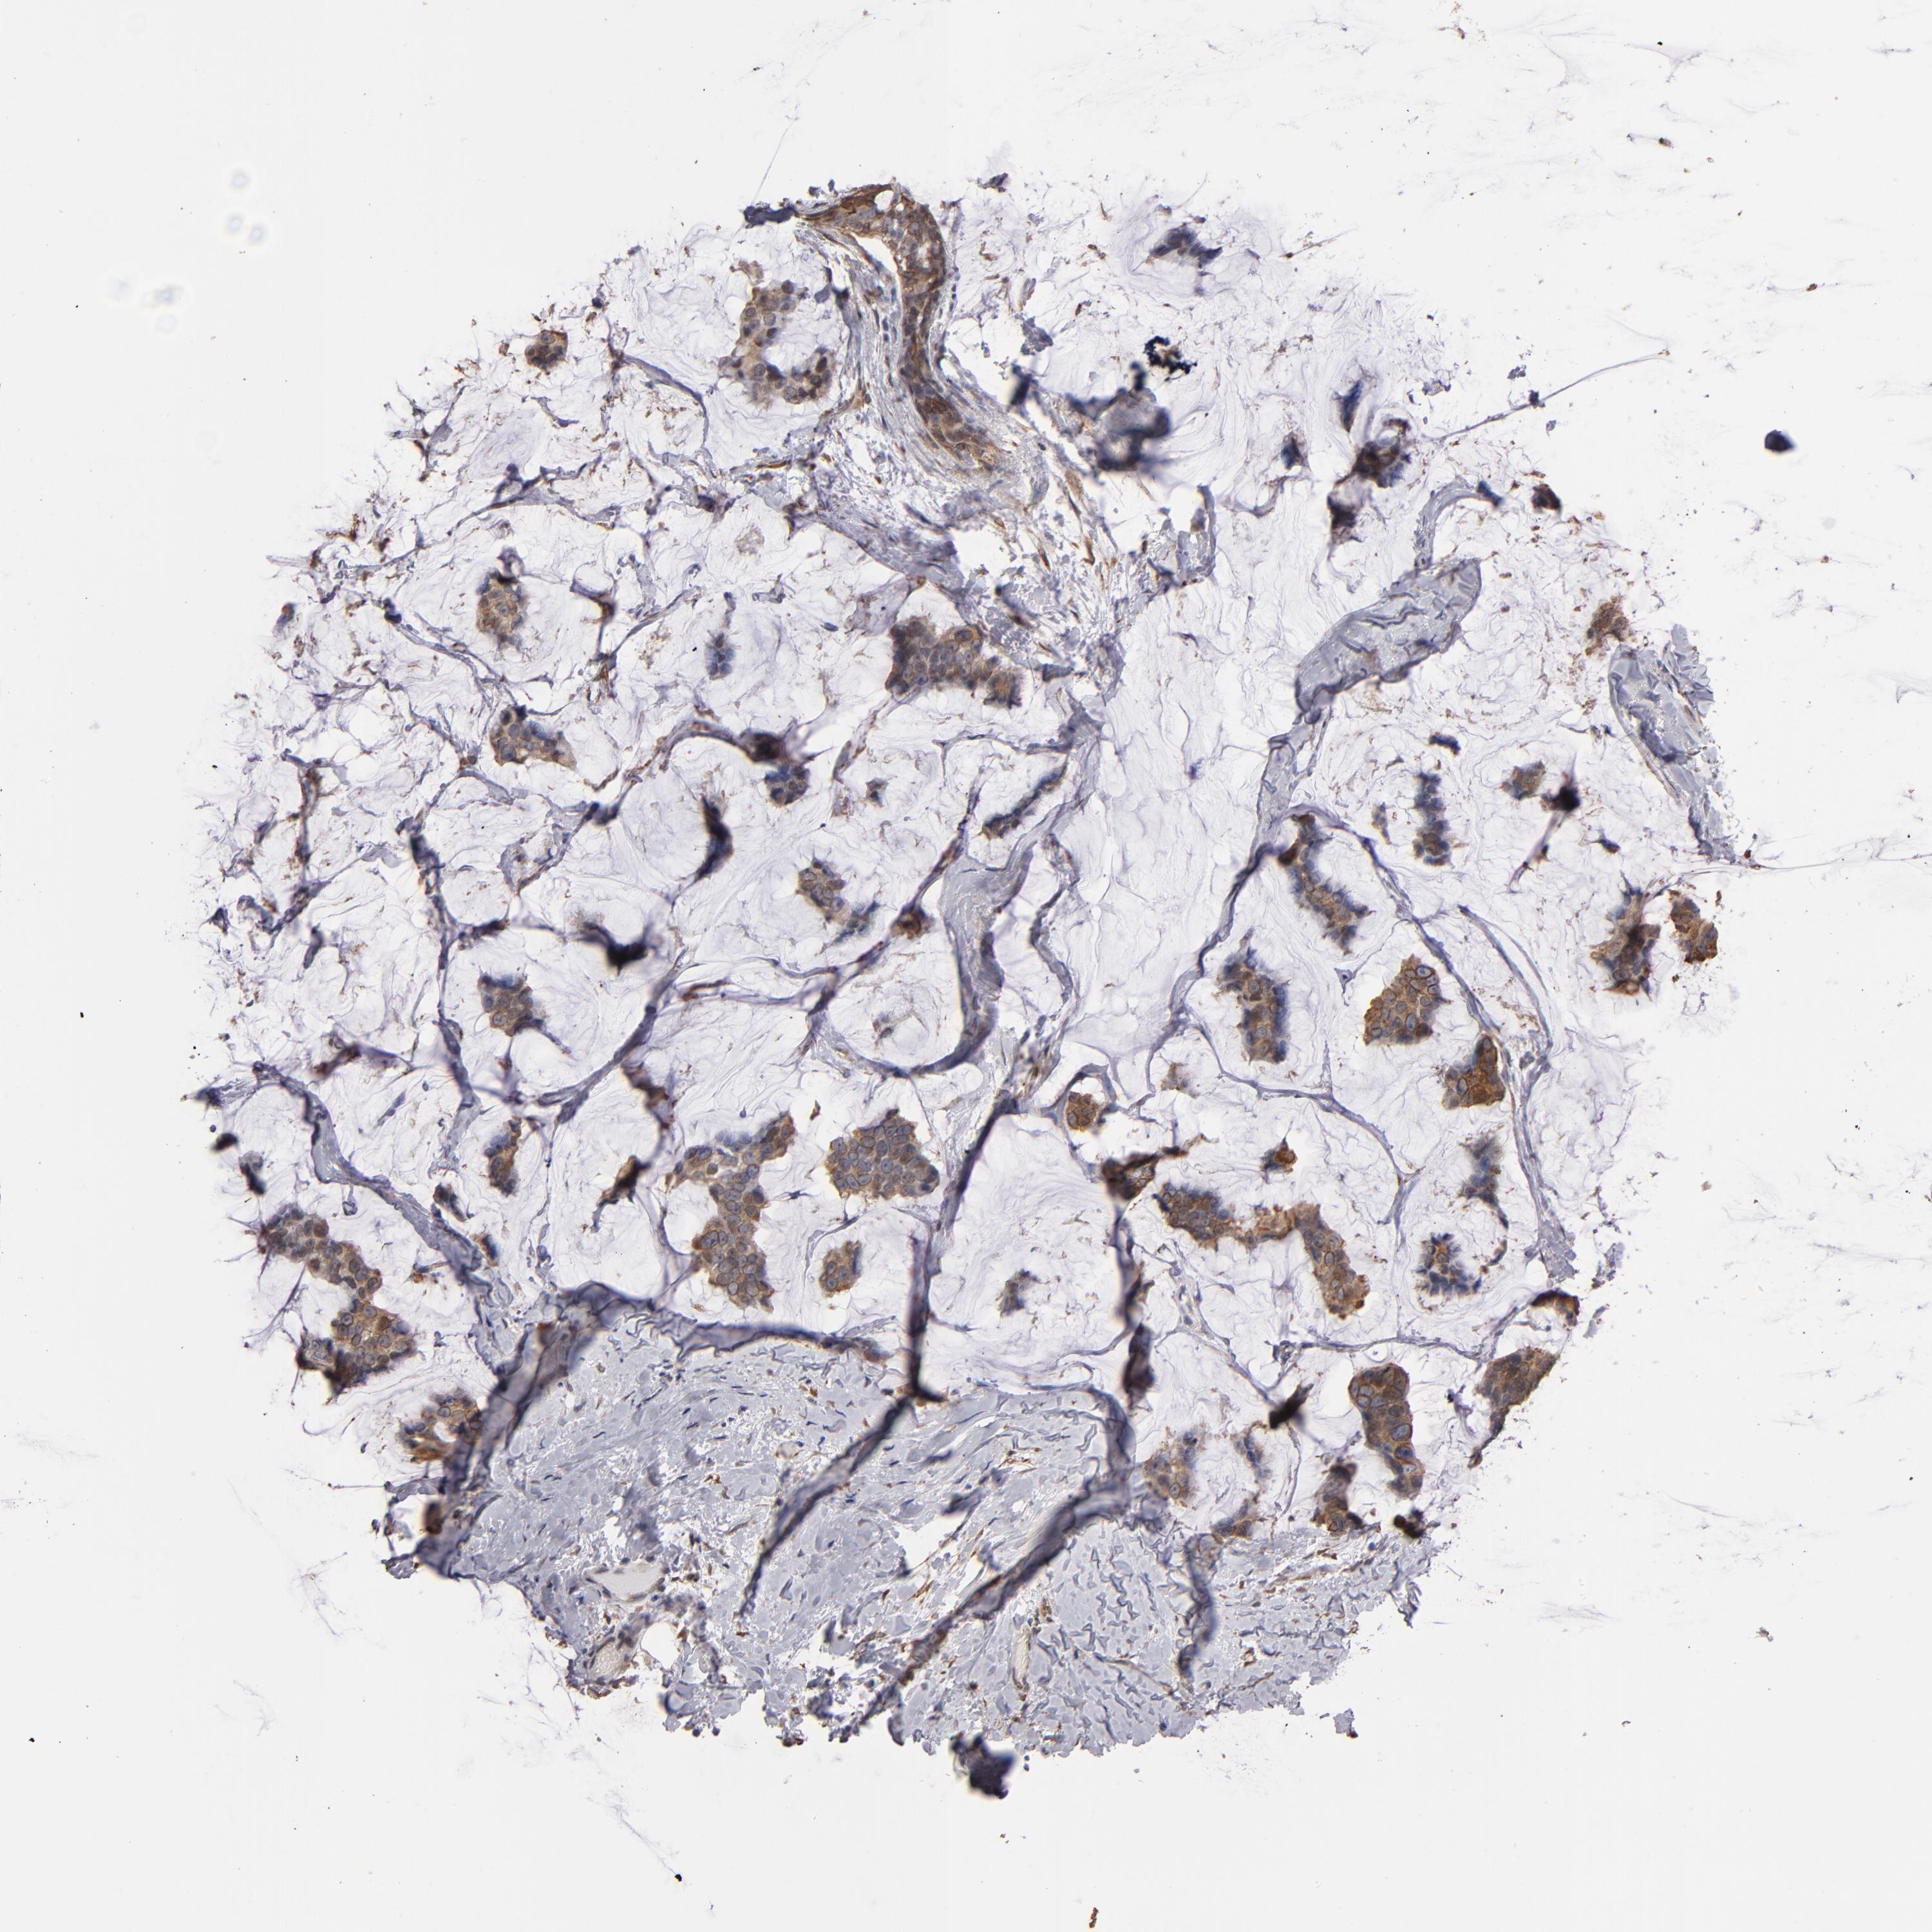

CANCER BREAST CANCER Show tissue menu

BRCA TCGA BRCA VALIDATION PROTEIN EXPRESSION